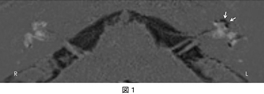

Gd造影による3T MRIを用いて内リンパ水腫の視覚化を可能にしました。 様々な難聴疾患において、内リンパ水腫存在の意義について検討を行っています(図1)。